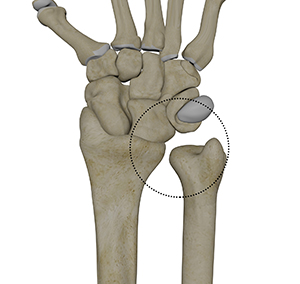

Distal radioulnar joint dislocation is an uncommon injury where the distal radius and ulna lose alignment, often caused by trauma, falls, or sports injuries. Patients typically present with wrist pain, swelling, deformity, and difficulty rotating the forearm. Diagnosis is made

The palmar midcarpal ligaments play an important role in stabilizing the midcarpal joint by connecting the proximal and distal carpal rows. Key ligaments in this group include the scaphotrapeziotrapezoid ligament, scaphocapitate ligament, triquetrocapitate ligament, and